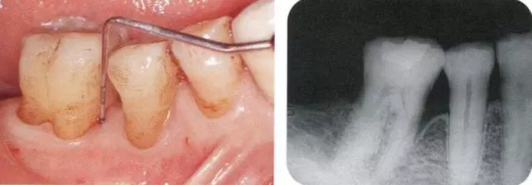

222.png

▲圖17-1,2

▲圖17-1 下頜右側(cè)磨牙區(qū)的邊緣嵴高度不齊,右下6近中有6mm的牙周袋。在這種邊緣嵴存在高低差的情況下,很容易引發(fā)食物嵌塞。

▲圖17-2 同部位的X光片。右下6近中有牙槽骨緣下牙周袋。